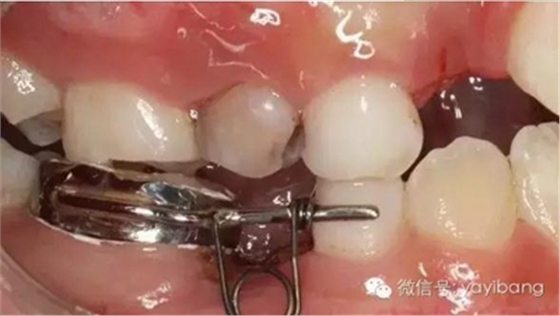

42、牙面拋光,試合制作好的間隙恢復器,將曲簧水平部分形成與牙面弧形一致,羧酸鋅水門汀粘結固定

43、粘結后的頰面觀